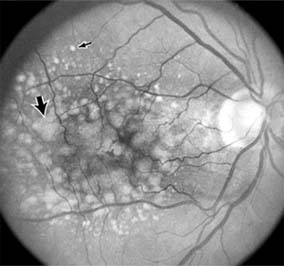

1. NONPROLIFERATIVE DIABETIC RETINOPATHY

Diabetic retinopathy is a progressive microangiopathy characterized by small vessel damage and occlusion. The earliest pathologic changes are thickening of the capillary endothelial basement membrane and reduction of the number of pericytes. Background diabetic retinopathy is a clinical reflection of the hyperpermeability and incompetence of involved vessels. The capillaries develop tiny dot-like outpouchings called microaneurysms, while the retinal veins become dilated and tortuous (Figure 10-20).

Figure 10-20

Figure 10-20: Background diabetic retinopathy with abundant macular exudate (open arrow), micro-aneurysms (small arrow), and intraretinal hemorrhage (large arrow).

Multiple hemorrhages may appear throughout different levels of the retina. Flame-shaped hemorrhages are so shaped because of their location within the horizontally oriented nerve fiber layer, while dot and blot hemorrhages are in the deeper retina, where cells and axons are vertically oriented.

Macular edema is the most frequent cause of visual loss among patients with background diabetic retinopathy. The edema is caused primarily by a breakdown of the inner blood-retinal barrier at the level of the retinal capillary endothelium, allowing leakage of fluid and plasma constituents into the surrounding retina. The edema may be focal or diffuse and appears clinically as thickened, cloudy retina with associated microaneurysms and intraretinal exudate. Circinate zones of yellow, lipid-rich exudate may form around clusters of microaneurysms and are most frequently centered in the temporal portion of the macula. While the prevalence of macular edema is 10% in the diabetic population as a whole, there is a dramatic increase in prevalence in eyes with more severe retinopathy.

With progressive microvascular occlusion, signs of increasing ischemia may be superimposed on the picture of background retinopathy and produce the clinical picture of preproliferative diabetic retinopathy. The most typical findings here are multiple cotton-wool spots, beading of the retinal veins, and irregular segmental dilation of the retinal capillary bed (intraretinal microvascular abnormalities). Closure of retinal capillaries surrounding the foveal avascular zone may cause significant ischemia, manifest clinically by the presence of large dark retinal hemorrhages and small thread-like macular arterioles. Eyes with macular edema and significant ischemia have a poorer visual prognosis-with or without laser treatment-than eyes with edema and relatively good perfusion.

The visual and electrophysiologic dysfunctions associated with diabetes probably result from the local vascular abnormalities and the systemic metabolic effects of the disease to which the retina is subjected. A characteristic blue-yellow color vision abnormality develops, and hue discrimination may be impaired. Contrast sensitivity may be reduced in patients, even in the presence of normal visual acuity. Visual field testing may show relative scotomas corresponding to areas of retinal edema and nonperfusion, and abnormalities in dark adaptation have also been described. Electroretinographic abnormalities bear a relationship to the severity of retinopathy and may aid in predicting progression of retinopathy. Fluorescein angiography is invaluable in defining the microvascular abnormalities of diabetic retinopathy (Figures 10-21 and 10-22). Large filling defects of capillary beds-"capillary nonperfusion"-show the extent of retinal ischemia (Figure 10-23) and are usually most prominent in the midperiphery. The fluorescein leakage associated with retinal edema may assume the petaloid configuration of cystoid macular edema or may be diffuse. Other fluorescein abnormalities include vascular loops and intraretinal shunts. The focus of treatment in patients with nonproliferative diabetic retinopathy and no macular edema is treatment of hyperglycemia and intercurrent systemic disease. A controlled clinical trial has shown that aldose reductase inhibitor therapy does not prevent progression of diabetic retinopathy. Focal argon laser treatment of discrete points of retinal leakage in patients with clinically significant macular edema, principally defined as thickening of the retina at or within 500 0x0003bcm of the center of the macula, reduces the risk of visual loss and increases the likelihood of visual improvement (see Chapter 24). Eyes with diabetic macular edema that is not clinically significant should usually be monitored closely without laser treatment. Since macular edema may be present with little or no change in visual acuity and requires slitlamp biomicroscopic retinal examination for full evaluation, primary health care providers should recognize the importance of prompt and early referral of diabetic patients to the ophthalmologist.

Figure 10-21

Figure 10-21: Fluorescein angiogram in nonproliferative diabetic retinopathy shows microaneurysms (arrow) and perifoveal retinal vascular changes.

Figure 10-22

Figure 10-22: Late phase fluorescein angiogram shows hyperfluorescence typical of noncystoid diabetic macular edema.

Figure 10-23

Figure 10-23: Fluorescein angiogram shows hypofluorescence from capillary drop-out (arrows) typical of ischemic diabetic maculopathy.